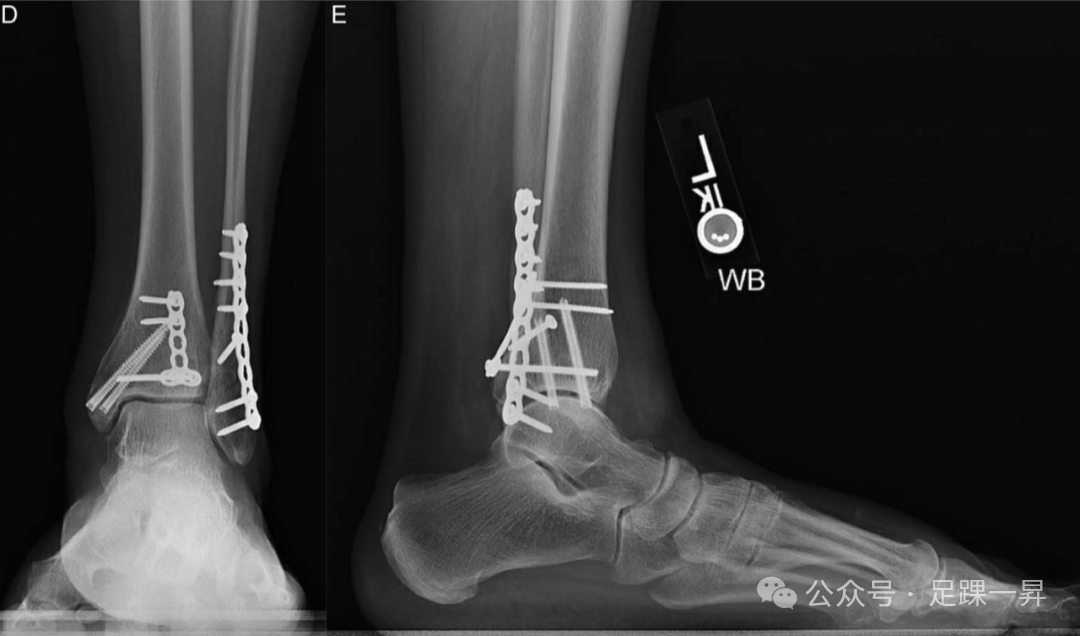

图5. 一例未使用下胫腓联合固定螺钉治疗的旋转性踝关节骨折伴踝穴增宽病例。术前非负重正位(A)和侧位(B)X线片显示三踝骨折伴踝穴增宽。(C)术中在解剖复位外踝、内踝和后踝后,通过外旋试验评估下胫腓联合稳定性,结果显示踝穴稳定。术后正位(D)和侧位(E)踝关节X线片显示踝穴维持良好,无增宽。